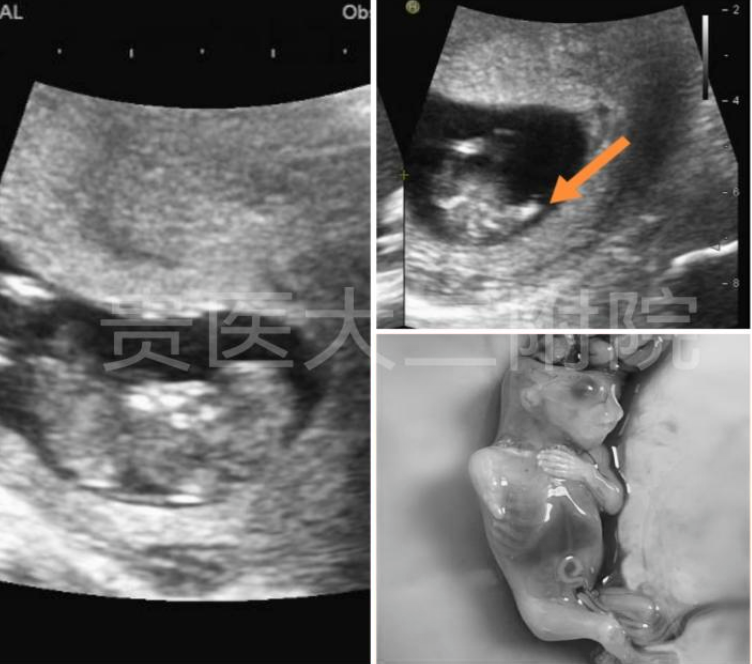

病例1:人体鱼序列综合征(又称并腿畸胎综合征)

图片